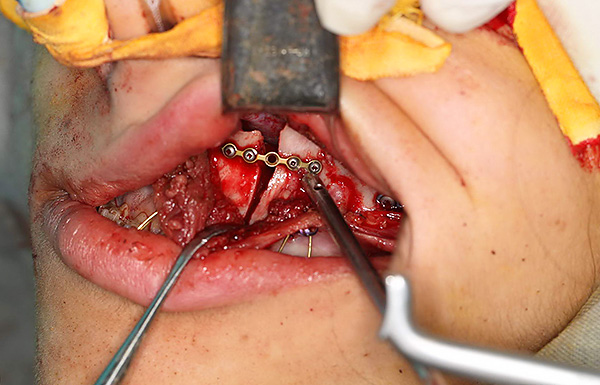

Chirurgia ortognatica come metodo di trattamento del morso permanente

A volte, per ottenere un morso ortognatico ideale, gli sforzi di un ortodontista da soli non sono sufficienti. Quando elabora un piano di trattamento, un ortodontista può immediatamente dire al suo paziente che avrà bisogno dell'intervento di un chirurgo maxillo-facciale. Se il paziente accetta questa fase, il piano di trattamento viene adattato in base alle esigenze del chirurgo per l'operazione. Quindi questi medici lavorano insieme e quando l'ortodontista crea tutte le condizioni necessarie per l'operazione, il chirurgo esegue un intervento chirurgico.

Le indicazioni per il trattamento chirurgico sono forme scheletriche gravi di malocclusione. Cioè, quando le cause dei problemi del morso non sono solo la posizione errata dei denti permanenti, ma anche la posizione errata o la dimensione delle ossa della mascella rispetto alla base del cranio.

In effetti, non è necessario aver paura della chirurgia ortognatica. Il chirurgo esegue tutte le incisioni e i tagli di ossa esclusivamente nella cavità orale, cioè non ci sono cicatrici sul viso. Dopo l'operazione, il chirurgo prescrive l'uso di speciali aste elastiche per fissare la nuova posizione delle ossa della mascella e consentire ai muscoli di abituarsi ai cambiamenti.

Il periodo di recupero dopo la chirurgia ortognatica è di circa 1 mese.Durante questo periodo, il paziente deve seguire una dieta rigorosa, non mangiare cibi solidi (le prime due settimane tutti gli alimenti dovrebbero essere liquidi). In ospedale dopo l'operazione, il paziente trascorre 5-7 giorni, quindi gli è permesso di tornare a casa e dopo 2 settimane una persona può tornare al lavoro, seguendo le istruzioni del medico.

Dopo 3-4 settimane, l'ortodontista, insieme al chirurgo, esamina il paziente e se i medici sono soddisfatti del risultato ottenuto, viene prescritta la rimozione del sistema di staffe.